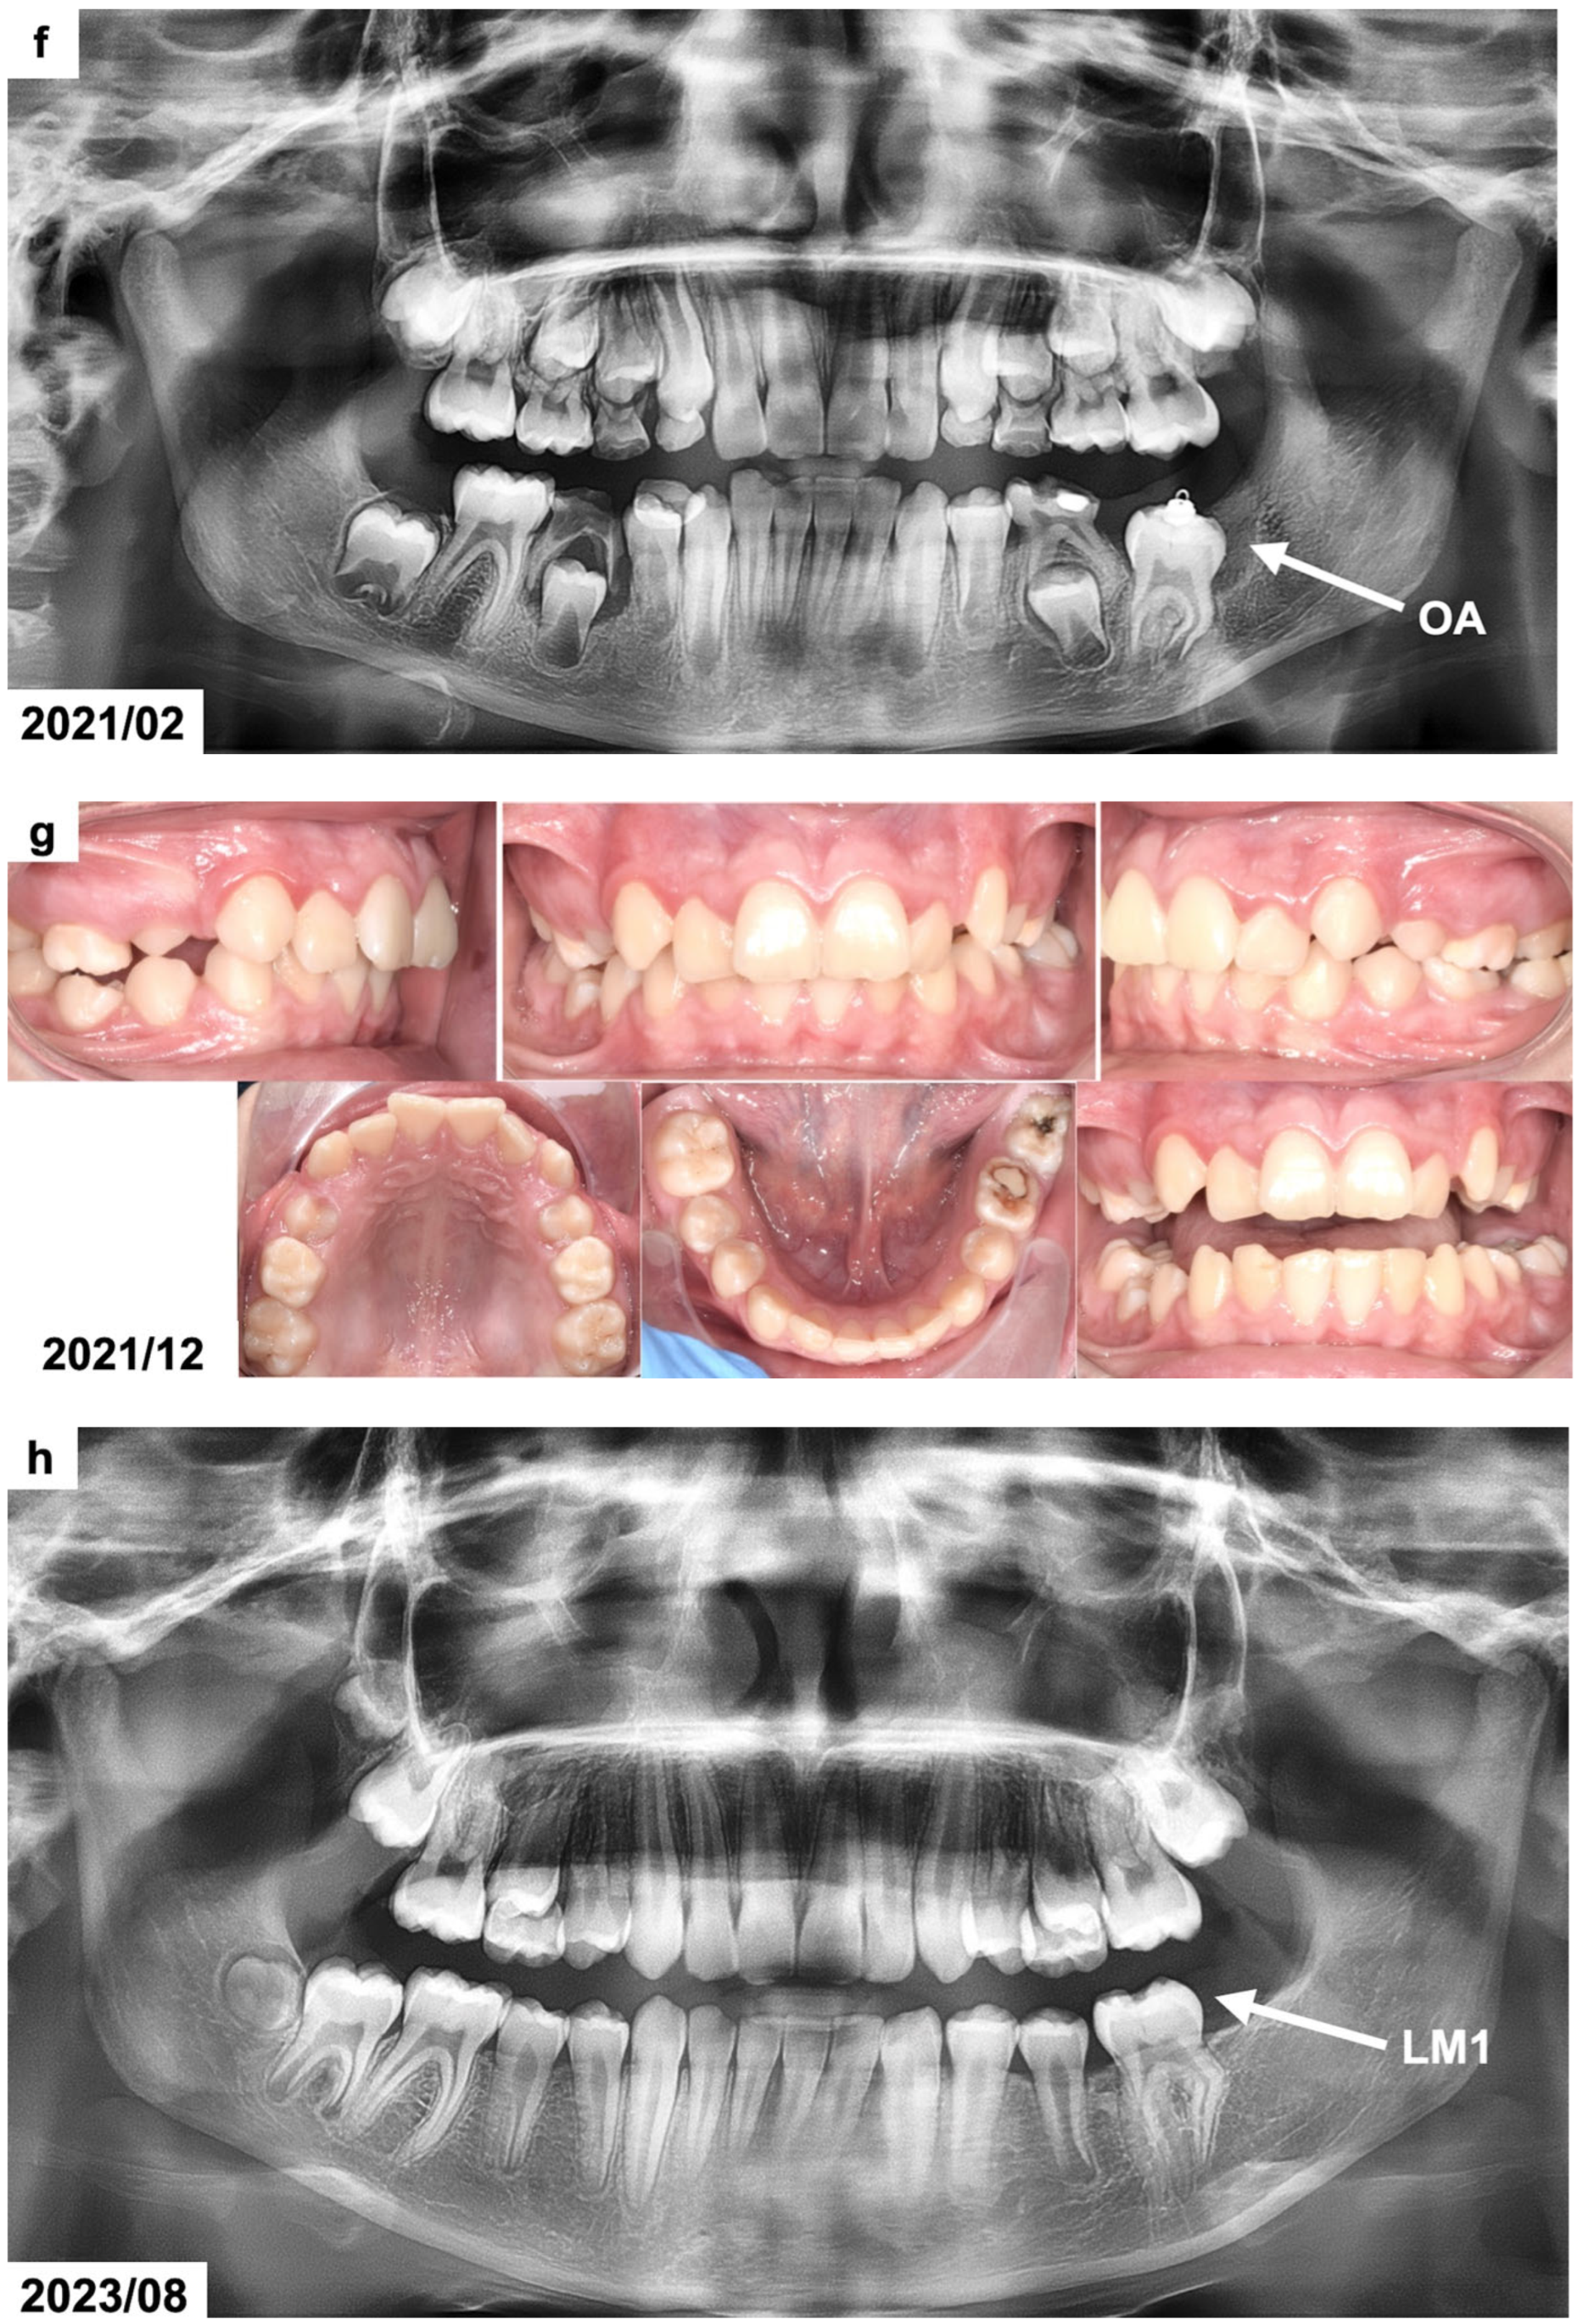

Figure 2.

(a) CBCT examination scans before the treatment presenting the odontogenic tumor in the right maxillary molar region. The patient was 15 years and 10 months old. (b) CBCT examination scans after the surgical removal of the tumor presenting the malposition of the impacted permanent upper right first molar. The patient was 16 years and 4 months old. (c) Panoramic radiograph after the treatment, presenting the impacted maxillary. The patient was 16 years and 7 months old. (d,e) Intraoral photographs 10 months after the surgical treatment before the use of orthodontic traction with a segmented fixed appliance. The patient was 16 years and 7 months old. (f) Intraoral photographs 1 year and 4 months after the orthodontic traction of the permanent upper right first molar. The patient was 17 years and 10 months old. (g) Panoramic radiograph 6 years after the surgical and orthodontic treatment. The patient was 24 years and 1 month old. (h) Intraoral photographs 6 years after the surgical and orthodontic treatment showing the erupted permanent upper right first molar and its position in the dental arch. The patient was 24 years and 1 month old. (i) CBCT examination scans 6 years after the surgical and orthodontic treatment presenting the erupted permanent upper right first molar and the absence of the alveolar bone at the site of the tumor removal. The patient was 24 years and 1 month old.

Cone-beam computed tomography (CBCT) was scheduled to determine the dimensions and position of the tumor. The CBCT examination showed a focal area with spherical radiopaque mass resembling the radiodensity of irregularly composed hard dental tissues/dentin and enamel tissues surrounded by a thin radiotransparent rim in the right maxillary molar region (Figure 2b). The dimensions of the lesion were 16 × 18 × 20 millimeters. The roots of the maxillary first permanent molar were fully developed. The tooth was impacted at distoangular position and its crown occlusally contacted with the tumor. The maxillary right second and third molars were absent. Based on the CBCT examination, the presence of a complex odontoma was suspected.

The treatment plan included surgical removal of the tumor and a combined surgical and orthodontic extrusion of the impacted maxillary molar. Bonding of an orthodontic button with a soft ligature for orthodontic traction was planned during the surgical removal of the tumor. The patient was not interested in the comprehensive orthodontic treatment to correct the posterior crossbite. Therefore, a segmented fixed orthodontic appliance in the maxillary posterior segment on the right side was planned, including the canine and both premolars. The orthodontic traction of the impacted molar was planned after the surgical removal of the tumor and lack of a spontaneous eruption. The patient was negative regarding the use of any temporary skeletal anchorage devices (TADs) from the start of orthodontic traction.

The result of a histopathological examination with H&E staining revealed the presence of mature tubular dentin with the spaces containing small amounts of enamel matrix or immature enamel—the mature enamel was removed during the decalcification process. Therefore, based on the clinical, radiological, and histological examinations, the diagnosis of a complex odontoma was confirmed. The impacted maxillary molar was left for observation, but no signs of its spontaneous eruption were seen for 10 months (Figure 2c–e). Therefore, an orthodontic traction with a segmented fixed appliance was planned (0.022 slot, American Orthodontics, Mini Master series). Orthodontic brackets were bonded on the maxillary canine and premolars on the right side. The teeth were aligned after 3 months, and a stainless-steel rectangular wire (0.017 × 0.022 SS) was placed. The impacted tooth was attached to the appliance using an elastomeric Powerchain attached to the metal ligature. The Powerchain was scheduled for changing every 5–6 weeks. The impacted molar was successfully extruded in the oral cavity after 1 year and 4 months (Figure 2f); however, the patient missed some appointments. The patient refused to continue her orthodontic treatment to correct the posterior crossbite after the extrusion of the impacted molar. The orthodontic appliance was debonded, and no retention was used. The patient missed scheduled follow-up appointments and presented for re-evaluation 5 years after finishing the orthodontic traction. The maxillary right first molar was present in the oral cavity without any signs of pathology (Figure 2g,h). The cone-beam computed tomography revealed the absence of the alveolar bone at the site of the tumor removal. It was recommended to perform bone augmentation procedures before further implantation (Figure 2i).